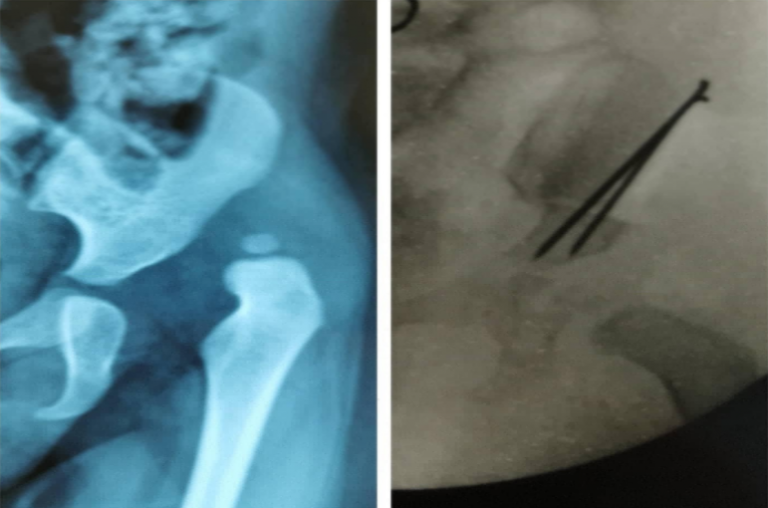

Displasia de cadera: Todo lo que necesitas saber

La displasia de cadera (DDC) es una patología que evoluciona con el tiempo y se produce durante la gestación. La cadera puede haberse formado bien durante las primeras